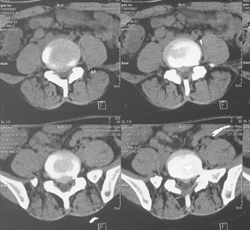

腰椎MRI示:L5S1椎间盘突出,左侧神经根受压。

(图)术前CT